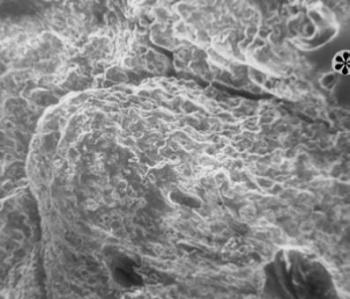

SEM-vizsgálatkor az elektronsugár az anyag felületét pásztázza, minden pontról képet alkot és a végeredmény a térhatású több ezer vagy több tízezerszeres nagyítású felvétel. A SEM-vizsgálatokhoz az anyag előkészítése egyszerűbb és jóval nagyobb mintákat lehet áttekinteni. A feldolgozás ilyenkor is az anyag rögzítésével, majd víztelenítésével kezdődik, ezt követően azt kiszárítják, felületére vékony aranyréteget visznek fel. A SEM feloldóképessége kisebb, mint a másik elektronmikroszkópé, azonban ezért bőven kárpótol a szép, részletdús kép, kiterjedtebben használható a paleopathologiában. Nemcsak ekto- és endoparazitákat (Stenn 1981), múmiaszöveteket, coprolithot, hanem osteomyelitises és daganatos csontokat (Schultz 1986), poroticus hyperostosist (Józsa és Pap 1991), hajmaradványokat (Pap és Józsa 1990), enthesopathiás csontkinövéseket stb. is vizsgáltak (29. ábra, 30. ábra), Schamall és mtsai (1999) pedig egy meningeoma differenciáldiagnosztikájában alkalmazták. Nemcsak emberi, hanem sokkal idősebb leleteken (80 millió éves őshüllő csontokban) Pawliczki (1976 és 1978) sejteket, kollagénrostokat, ércsatornákat tudott kimu tatni. Bár mind a TEM, mind a SEM bonyolult, drága vizsgálat, mégis kezdenek elterjedni az őskórtanban és olyan új lehetőségeket nyitottak, amelyeknek csak töredékével éltünk ez ideig.

29. ábra. Enthesopathiás csonttaraj pásztázó elektronmikroszkópos képe. 10–11. századból való sarokcsont. SEM 130× nagyítás